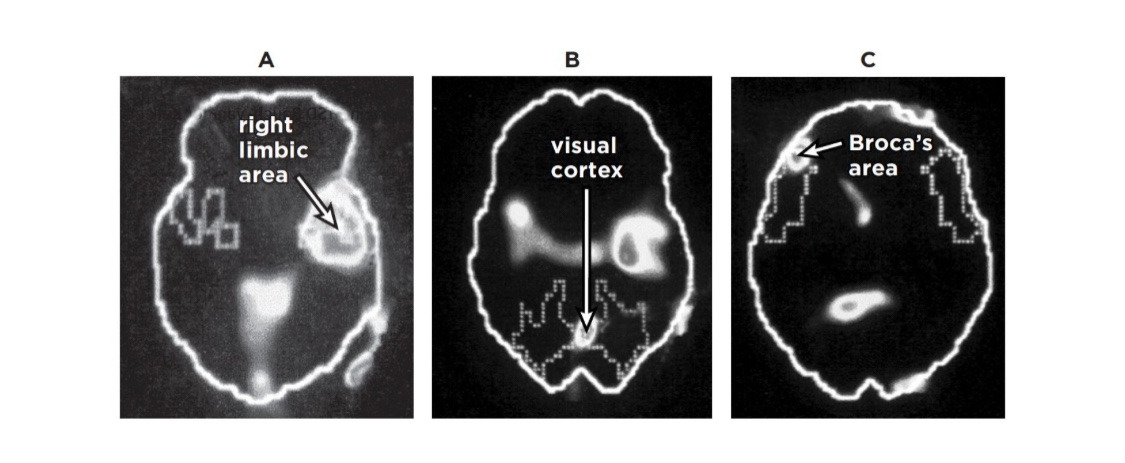

트라우마가 떠오른 뇌의 모습

사진 A에서 밝게 빛나는 부분은 변연계이고, B는 활성이 증가한 시각 피질을 나타낸다. 사진 C에서는 뇌의 언어 센터인 브로카 영역의 활성이 크게 감소한 모습을 볼 수 있다. 즉, 강렬한 감정은 변연계, 특히 편도체 부위를 활성화시킨다. 편도체는 우리에게 곧 닥칠 위험을 경고하고 체내 스트레스 반응을 활성화시키는 곳. 공포 센터로 불리는 이 부위가 활성화되면 스트레스 호르몬에 의한 일련의 반응들이 촉발되고 혈압, 심장 박동 수, 산소 흡입량을 늘리는 신경 자극이 일어난다. 모두 신체가 싸움-도주 반응을 준비하는 과정이다. 그리고 좌뇌 전두엽 피질 중 브로카 영역이라 불리는 말하기를 담당하는 뇌의 영역은 활성이 크게 감소되었는데. 이는 기능을 하지 못함으로써 생각과 기분을 말로 표현할 수 없다는 의미. 따라서 트라우마가 생긴 사람들은 시간이 많이 흐른 뒤에도 과거에 무슨 일이 있었는지 말하려고 하면 엄청난 괴로움을 느끼게 된다. 이들의 신체는 공포와 격렬한 분노, 무기력감을 다시 경험하고 동시에 싸우거나 도망가고 싶은 충동을 느끼지만, 이러한 감정을 말로 설명하는 건 거의 불가능하다.

정신적 외상을 입은 사람들이 과거의 일을 떠올리게 만드는 자극을 접하면, 우반구는 그 트라우마 상황이 지금 일어난 것처럼 반응한다. 그러나 좌뇌가 적절히 기능하지 못하는 상태라 당사자는 자신이 과거를 다시 경험하고 있으며 과거 일이 재현되고 있다는 사실을 인지하지 못한 채, 그저 격분하거나 겁에 질려 펄펄 뛰고 수치스러워하고 그 자리에 얼어붙어 버린다.